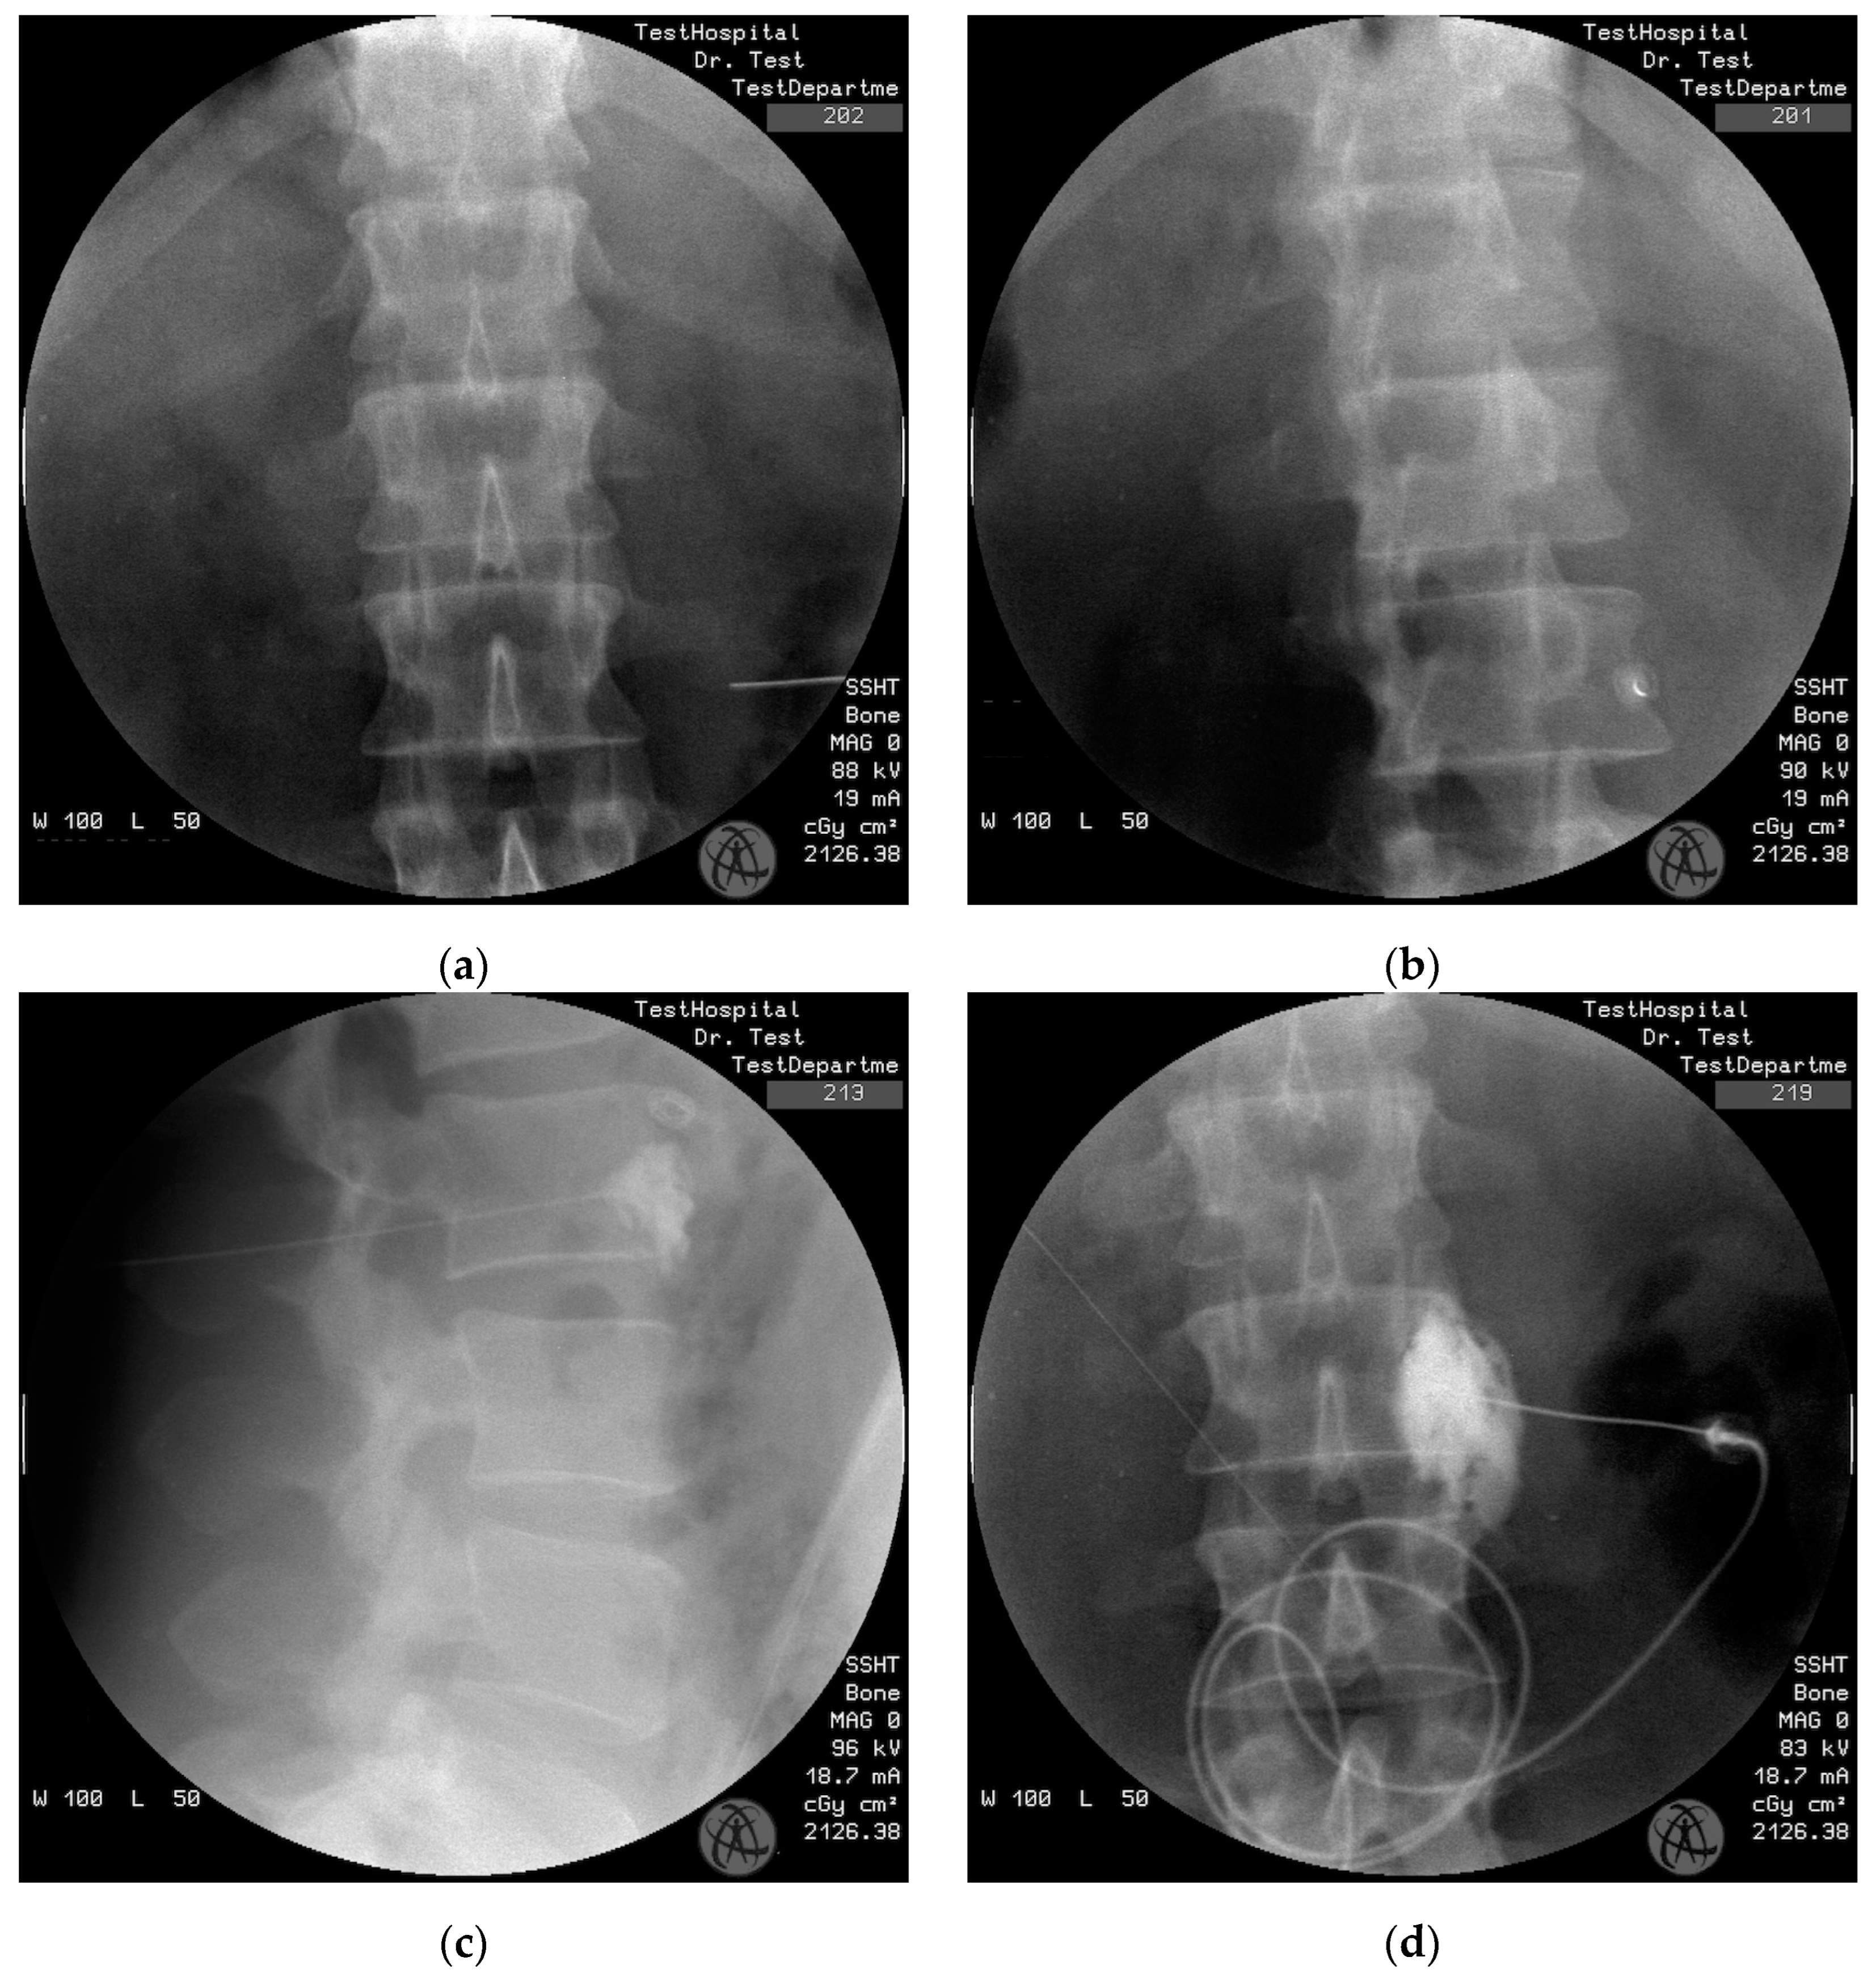

2.4. Procedure of Lumbar Sympathetic Block